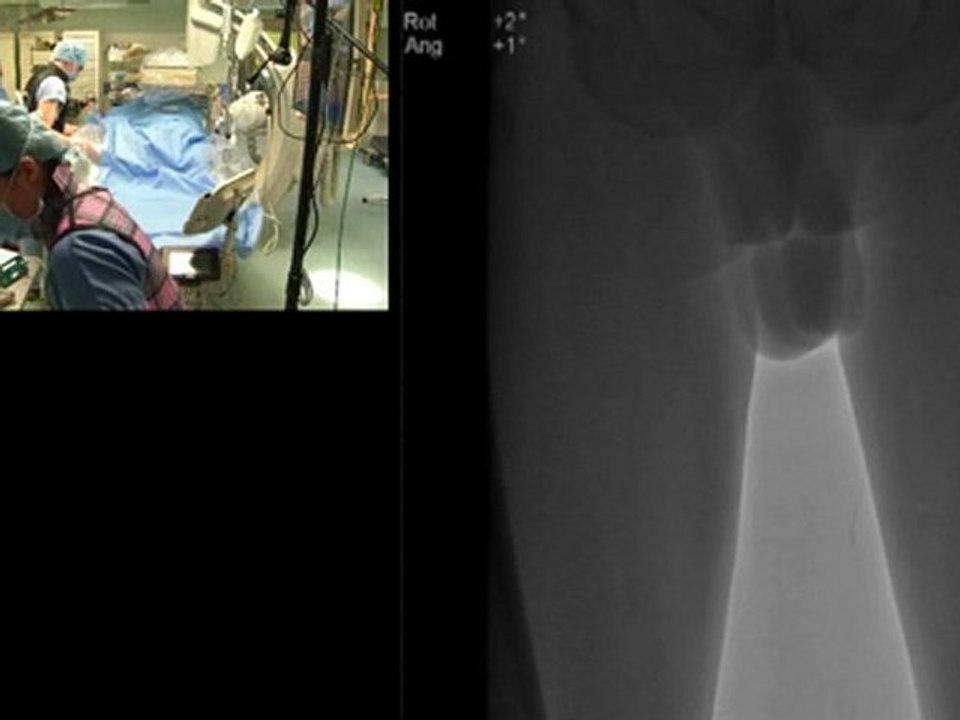

13 carotid revascularization case 1 left carotid artery stenting occluded rica incathlab.com